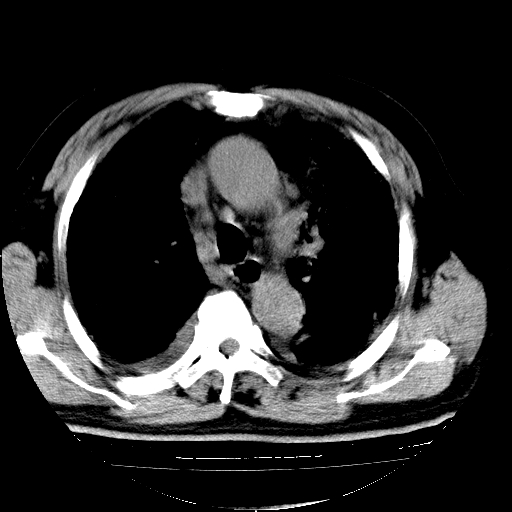

男,68岁,咳嗽、胸闷、发烧三天,查体:双肺散在湿罗音。

首先考虑特发型肺间质纤维化;两侧少量胸腔积液。

依据:1、两肺广泛条索状、网格状、蜂窝状改变。